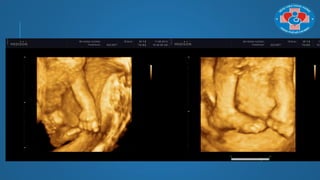

MỘT SỐ VỊ TRÍ THỰC HIỆN SIÊU ÂM

3D/4D THƢỜNG DÙNG

Để khảo sát tứ chi

MỘT SỐ VỊTRÍ THỰC HIỆN SIÊU ÂM 3D/4D THƢỜNG DÙNG Để khảo sát tứ chi